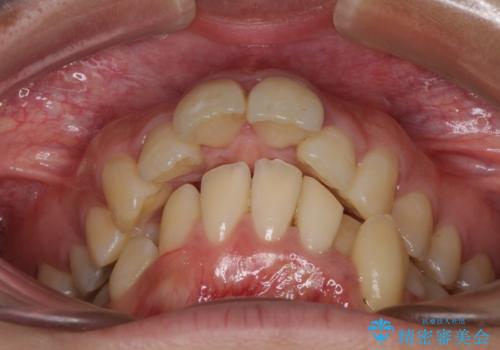

舌の突出癖が顕著で、上顎歯列は完全なV字型となっている状態でした。

下顎歯列にも八重歯があり、上下左右の第一小臼歯4本を抜歯して、ワイヤー装置にて矯正治療を行うこととしました。